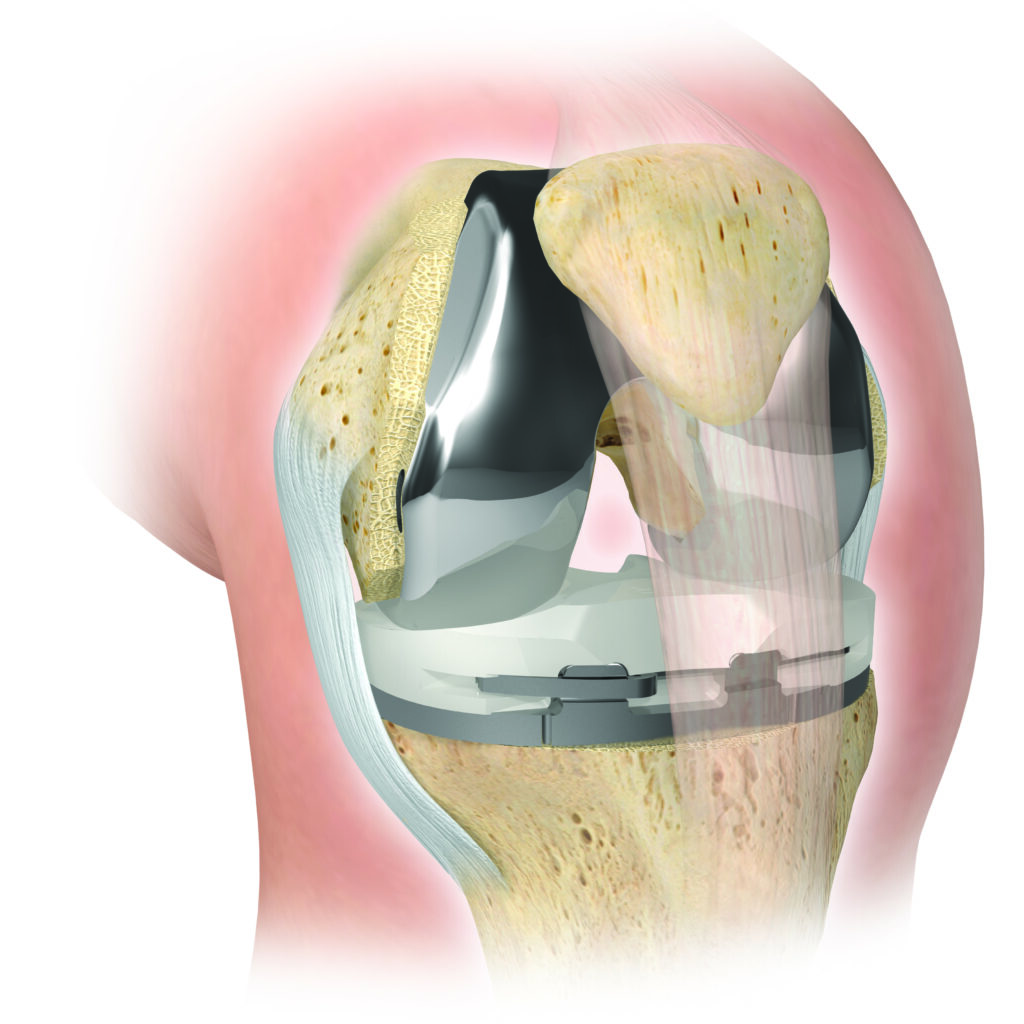

Bei der Kniegelenksarthrose wird die verschlissene Knorpeloberfläche der Gelenkpartner durch eine Metalloberfläche ersetzt („Oberflächenersatz“). Dabei wird auf den in mehreren Ebenen exakt zugesägten Oberschenkelknochen eine Metallkappe aufgeschlagen, am Unterschenkel eine dünne Scheibe mit dem verschlissenen Knorpel entfernt und mit einer Metallplatte versehen. Als Gleitschicht zwischen beiden Komponenten dient ein sog. Inlay aus Polyethylen.

Ist nur die Innenseite des Kniegelenks verschlissen, kann eine sog. Unicondyläre Endoprothese („Schlittenprothese“) eingesetzt werden.

Eine zunehmende Bedeutung kommt der Individualisierung in der Endoprothetik zu. Bereits seit 2010 verwendet Herr Dr. M. Zoepp patientenspezifsche Implantate und Instrumente bei Knieoperationen. Dazu wird ambulant eine CT- oder MRT-Aufnahme angefertigt, auf deren Basis nach individueller Planung im 3-D-Druckverfahren OP-Schablonen hergestellt werden, die Ihrem Knie exakt angepasst werden und eine genauere Umsetzung der OP-Planung ermöglichen als herkömmliche OP-Verfahren. Der Zeitaufwand zur Fertigung dieser Instrumente beträgt ca. 4-6 Wochen. Auch die Herstellung individuell angepasster Endoprothesen ist möglich.

Bei stärkeren Achsabweichungen (X- oder O-Bein) verwenden wir Endoprothesen, bei denen Ober- und Unterschenkelkomponente durch einen Zapfen miteinander verbunden sind (sog. teilgekoppelte KTEP).